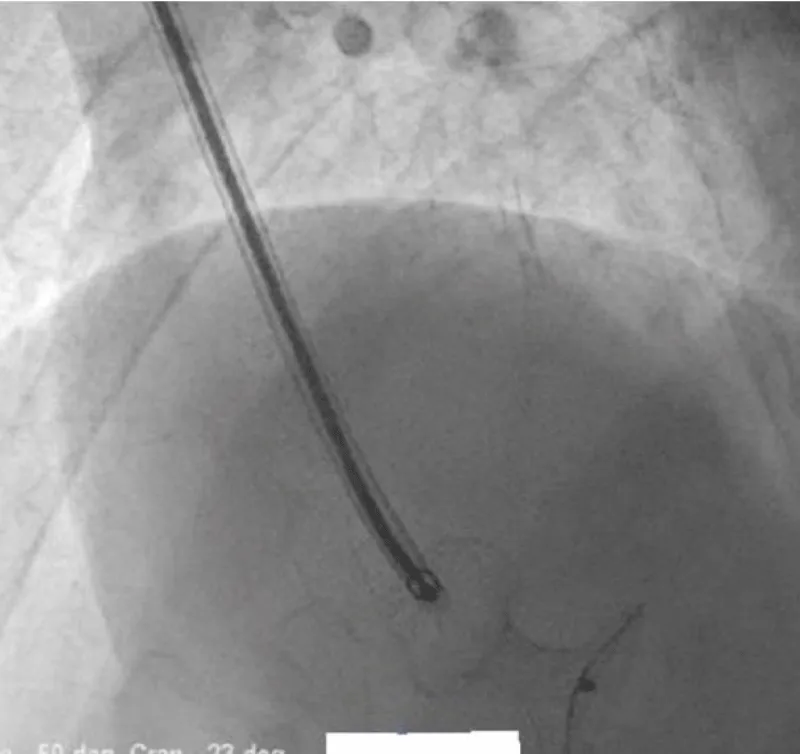

There was no use of transesophageal echocardiography due to the unavailability of a suitable probe. Left Ventricular angiogram was done to determine the exact location of the VSR (Figure 2). Cannulation of the right femoral artery and right internal jugular vein or right femoral vein was performed using the Seldinger technique. A guidewire (03500 Terumo guidewire) was introduced from the femoral artery, through the aorta into the left ventricle, and advanced through the VSR into the right ventricle and pulmonary artery. A second snaring wire was introduced through the vein (Either jugular or femoral) to connect to the guidewire in the pulmonary artery. By retracting the snared wires, the guidewire now forms an arteriovenous (AV) loop. The delivery sheath was advanced from the venous side loop over the guidewire through the VSR into the left ventricle. Correct positioning of the delivery sheath is confirmed in fluoroscopy/TTE. The guidewire is then retracted leaving the delivery sheath in position. After the echocardiographic confirmation occluder device was deployed across VSR using the delivery sheath (Figure 3). Correct positioning of the device and closure was confirmed by transthoracic echocardiography and/or fluoroscopy. If placement is satisfactory, the occluder is released. Post-procedure Left ventricular angiography and transthoracic echocardiography (Figure 4) were done to confirm the position and to rule out the presence of any residual shunt. We did not perform transoesophageal echocardiography for delineation of post-MI VSR, in any of the patients of our series due to the lack of availability of probes. In two cases we did not use any contrast agent (angiography) to delineate VSR because both patients had very high levels of urea and creatinine. Out of 11, in 10 cases, we made use of the femoral-jugular mode of access and created an AV loop. In one case we made a femoral arterio-venous loop. The veno-venous loop though described in literature was not used in this study.

Figure 3: After echocardiographic confirmation occluder device deployed across VSR using the delivery sheath.